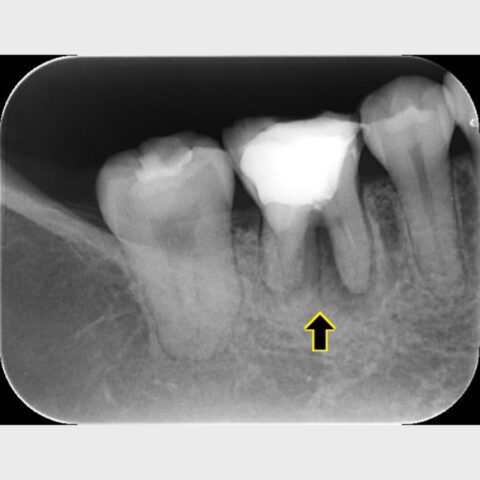

レントゲンで根の股の部分に歯質がなく、パーフォレーションがおきています。

それが原因で根尖病変ができ、骨が溶けてしまっているのでレントゲンで黒く映ります。